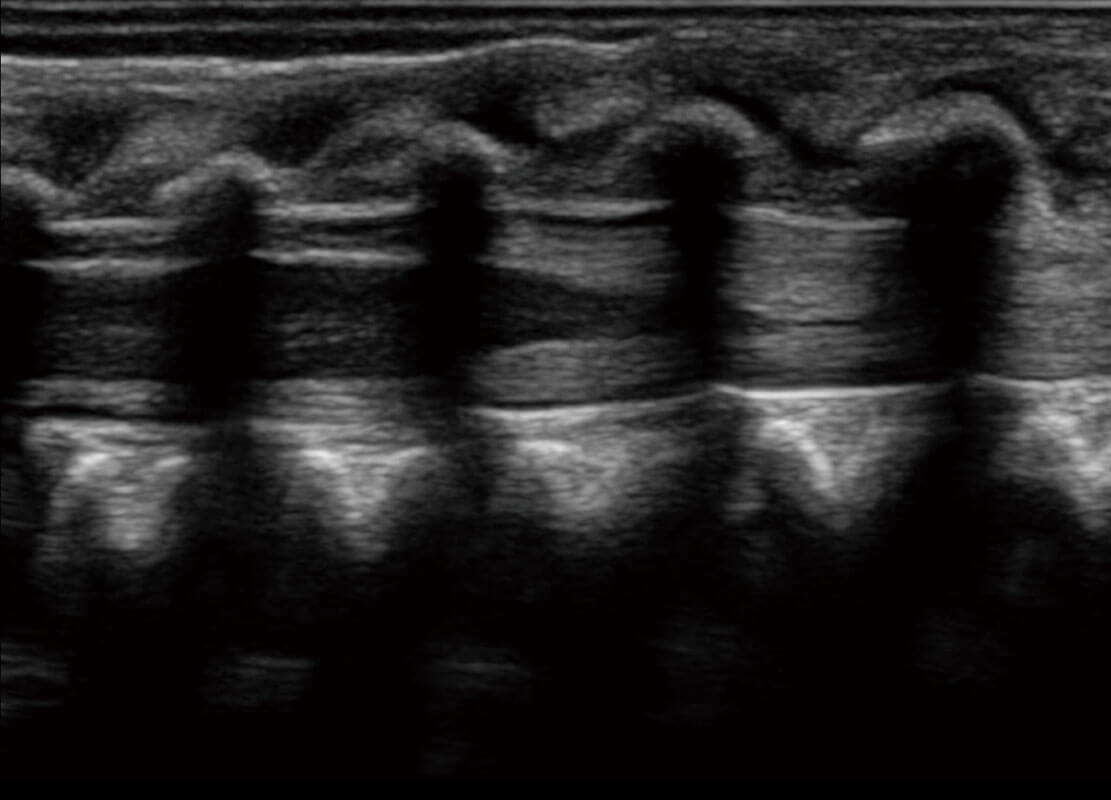

早孕-胎心

四腔切面